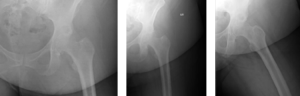

A 67-year-old Caucasian female weighing 190lbs diagnosed with osteo/degenerative arthritis received Advita’s Alteon® Neck Preserving Stem with a Biolox®delta femoral head and Novation® Crown Cup acetabular shell. The patient went under general anesthesia using a direct anterior surgical approach with an incision size of 10cm. There was an estimated blood loss of 150cc and surgery duration was 41 minutes. The patient was discharged after one day postoperative with a walker to in-home care for rehabilitation.

Pre-Op AP Pelvis

Harris Hip Score 37 (max=100) | Oxford Hip Score 19 (max=48)

6-Week Post-Op

Harris Hip Score 98 (max=100) | Oxford Hip Score N/A

3-Month Post-Op

Harris Hip Score 94 (max=100) | Oxford Hip Score 43 (max=48)

1-Year Post-Op

Harris Hip Score 100 (max=100) | Oxford Hip Score 48 (max=48)

CONCLUSION

Before surgery, this patient presented low Harris Hip and Oxford Hip scores. Once she reached her one-year follow up, her scores increased by more than 63.0 percent on the Harris Hip and 60.4 percent on the Oxford Hip. The patient is satisfied with her total hip replacement with the direct anterior approach, which has been associated with faster functional recovery than the posterolateral approach. The outcomes of her surgery continue to be followed annually. •